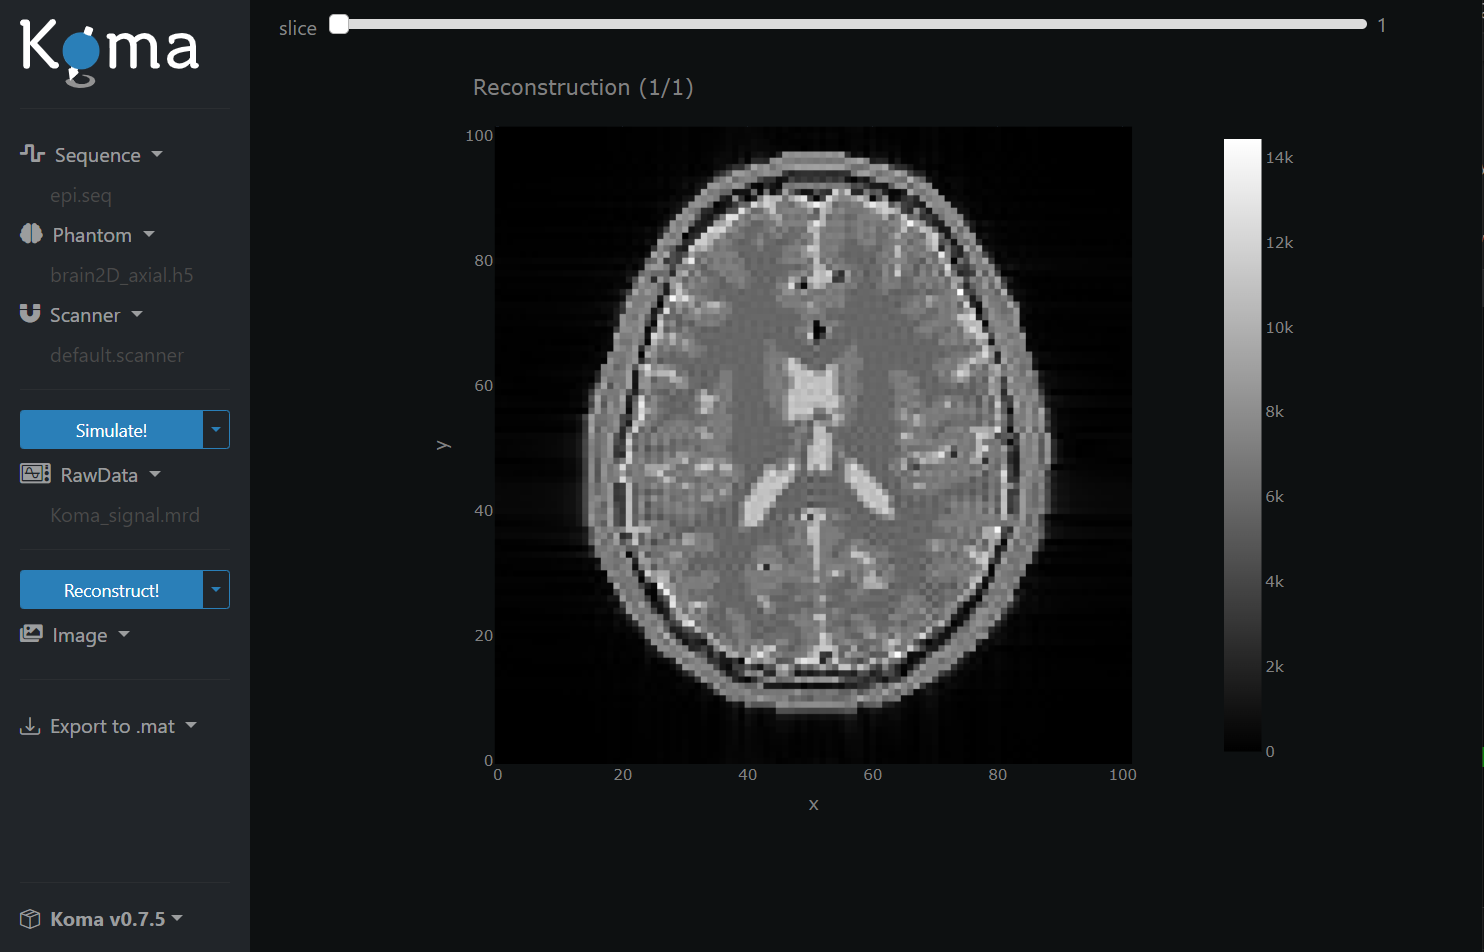

Then, press the Reconstruct! button and wait until the reconstruction ends. Now you have reconstructed an Image from the Raw Signal and you should see the following in the GUI:

Congratulations, you successfully simulated an MRI acquisition! 🎊